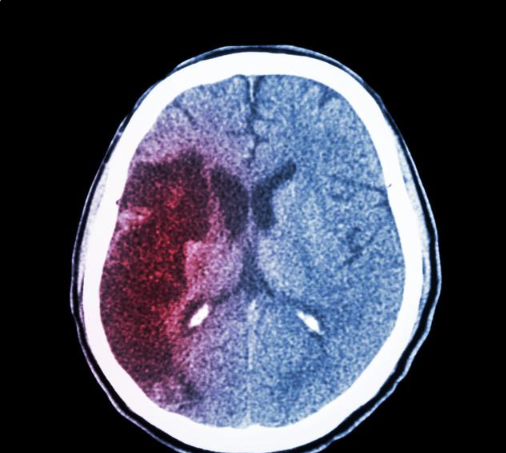

经检查发现,她的左枕叶脑出血50毫升,是很严重的脑溢血了。